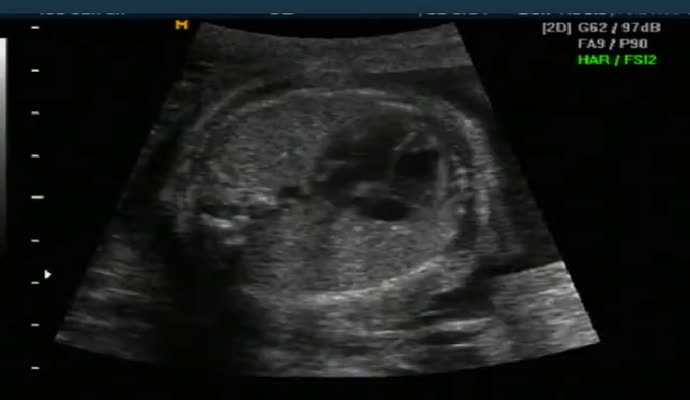

아래는 초음파 영상이기는 하지만 그렇게 올려진 영상 샘플입니다.

ob_usg_normal.mp4.jpg (17.74 KB, 다운수: 414)

ob_usg_normal.mp4

5.07 MB, 다운수: 787